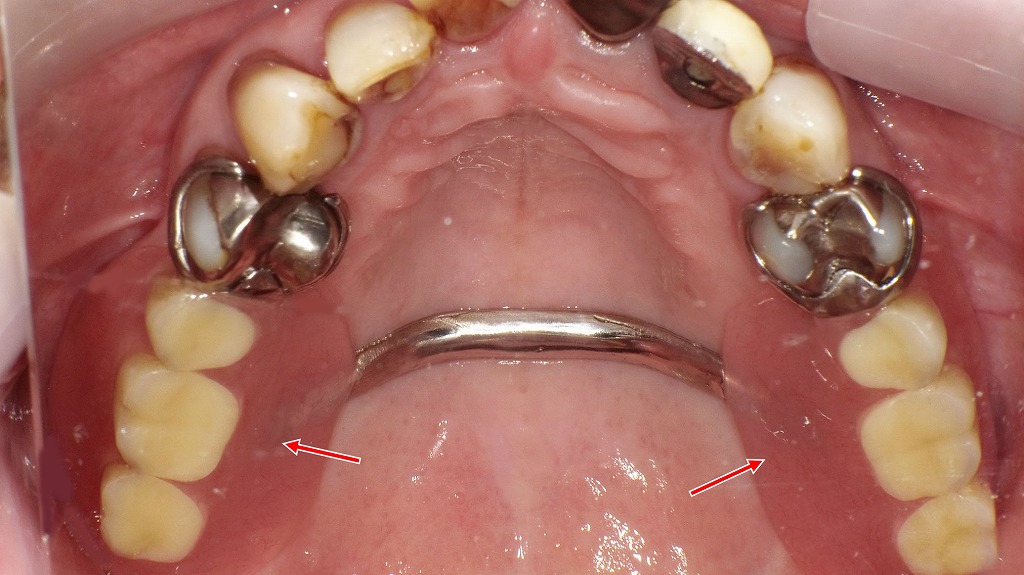

抜歯後の選択肢|保険適用の部分入れ歯

奥歯を抜歯した後の治療法のひとつが、保険適用の部分入れ歯です。写真は、金属のバネ(クラスプ)で歯に固定し、上顎はパラタルバーで安定性を高めた設計です。比較的早く作製でき、費用を抑えられる点がメリットですが、装着感や見た目、噛む力には限界があります。抜歯後は放置せず、口腔内の状態やライフスタイルに合った補綴方法を検討することが大切です。